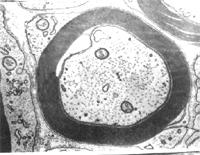

有髓神经纤维描述:神经纤维平行排列成束,在每条神经纤维的中央有轴突,外包雪旺氏细胞形成的髓鞘,神经纤维每隔一定距离有一环状的缩细部称郎飞氏结,此处髓鞘中断,雪旺氏细胞膜直接与轴突相贴。在神经纤维间可看到椭圆形的细胞核,是结缔组织中的成纤维细胞核,染色较深。

有髓神经纤维(myelinated nerve fiber)由轴突(或树突)、髓鞘、神经膜构成。髓鞘(myelin sheath)及神经膜(neurolemma)呈鞘状包裹在轴突的周围。在轴突的起始部无髓鞘包裹,称此部为起始段(initial segment)起始段远侧的轴突部分,髓鞘呈节段包卷轴突,形似藕节,其间断部位,轴膜裸露,,可发生膜电位变化,称此部位为神经纤维节(node of nerve fiber),又称郎飞结(Ranvier node)。两个相邻结之间的一段,称结间体(internode),长约0.5~lmm,它是由一个施万细胞所形成的髓鞘及其周围的神经膜构成。施万细胞核呈长椭圆形,位于髓鞘边缘的少量胞质内。髓鞘主要是由类脂质和蛋白质所组成,称为髓磷脂(myelin)在常规染色标本上,因髓鞘中的类脂被溶解,仅见残存的蛋白质呈网状,称神经角演网(neurokeratin network)。在锇酸浸染标本上,髓鞘呈黑色,其中还可见数个呈漏斗形的斜裂,称髓鞘切迹(incisure of myelin)或施-兰切迹(Schmidt-Lanterman incisure)。电镜下,髓鞘为明暗相间的同心圆板层排列。髓鞘有保护和绝缘作用,可防 止神经冲动的扩散。

(1)周围神经系统的有髓神经纤维:这种神经纤维的轴突,除起始段和终末外均包有髓鞘。髓鞘分成许多节段,各节段间的缩窄部称郎氏结(Ranvier node)。轴突的侧支均自郎氏结处发出。相邻两个郎氏结之间的一段称结间体(internode)。轴突越粗,其髓鞘也越厚,结间体也越长。每一结间体的髓鞘是由一个施万细胞的胞膜融合,并呈同心圆状包卷轴突而形成的,电镜下呈明暗相间的同心状板层。髓鞘的化学成分主要是类脂和蛋白质,称髓磷脂(myelin)。髓磷脂中类脂含量很高,约占80%,故新鲜髓鞘呈闪亮的白色,但在常规染色标本上,因类脂被溶解,仅见残留的网状蛋白质。若标本用锇酸固定和染色,髓磷脂保存,髓鞘呈黑色,在其纵切面上常见一些漏斗型的斜裂,称施-兰切迹(Schmidt-Lantermann incisure)。

施万细胞的胞核呈长卵圆形,其长轴与轴突平行,核周有少量胞质。由于施万细胞包在轴突的外面,故又称神经膜细胞(neurilemmal cell),它的外面包有一层基膜。施万细胞最外面的一层胞膜与基膜一起往往又称神经膜(neurilemma),光镜下可见此膜。

髓鞘的形成:在有髓神经纤维发生中,伴随轴突一起生长的施万细胞表面凹陷成一纵沟,轴突位于纵沟内,沟缘的胞膜相贴形成轴突系膜(mesaxon)。轴突系膜不断伸长并反复包卷轴突,把胞质挤至细胞的内、外边缘及两端(即靠近郎氏结处),从而形成许多同心圆的螺旋膜板层,即为髓鞘。故髓鞘乃成自施万细胞的胞膜,属施万细胞的一部分。施万细胞的胞质除见于细胞的外、内边缘和两端外,还见于髓鞘板层内的施-兰切迹。该切迹构成螺旋形的胞质通道,并与细胞外、内边缘的胞质相通。